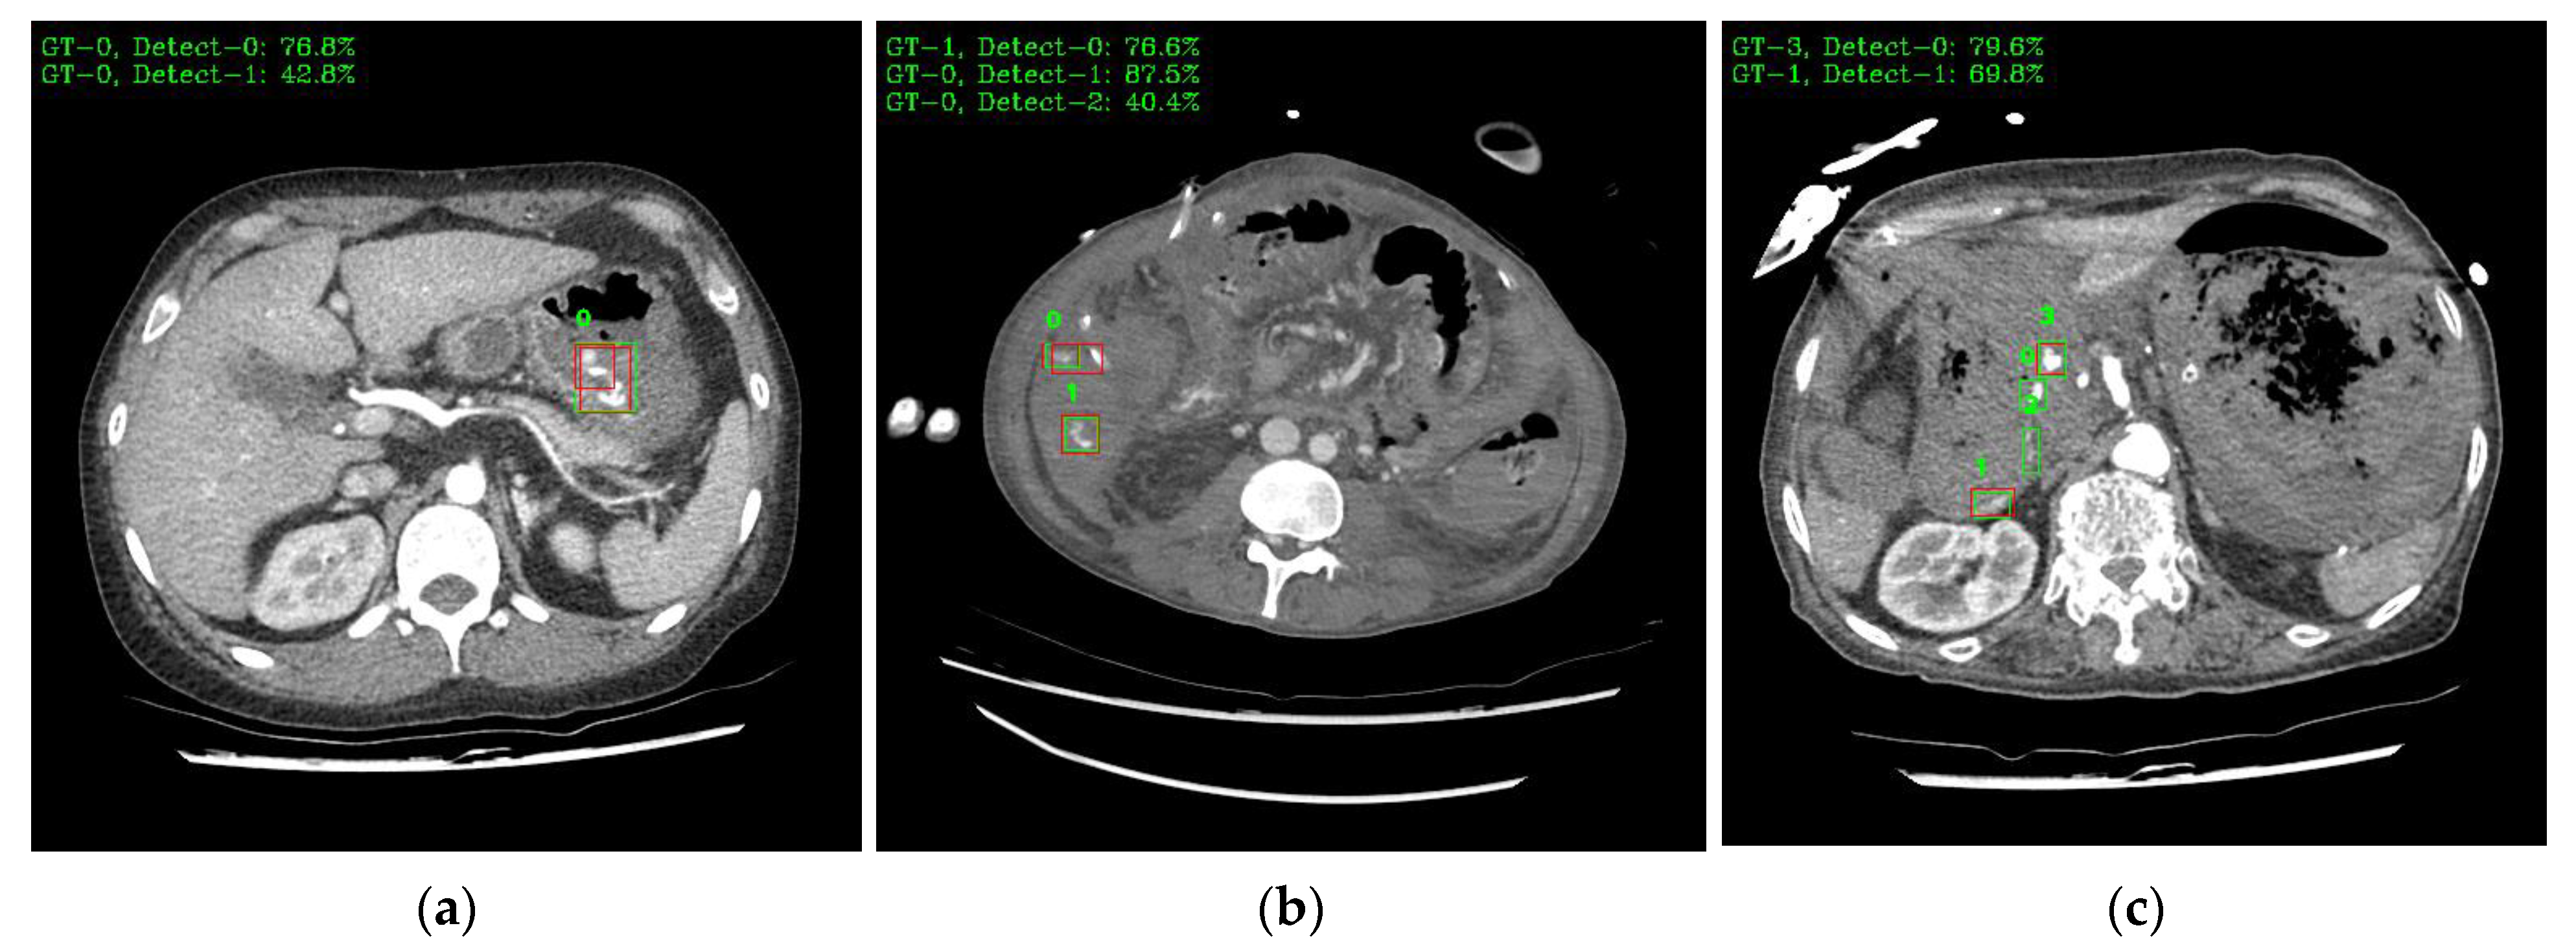

Figure 9 shows a visual representation of the results of lesion detection using the AH detector. Each image used for detection contains at least one GT-Box (green rectangle), which is the correct region. A P-Box (red rectangle), which is the detected region, is displayed according to the number of lesions detected and is not displayed when detection fails. The green text in the upper left corner of each image shows the index number of the GT-Box, index number of the detected P-box, and information about the IoU score. For example, Figure 9a shows that, for one GT-Box with a GT-Box index number of 0 (GT-0), two P-Box index numbers (Detect–{0, 1}) were generated with IoU scores of 76.8% and 42.8%. In addition, as shown in Figure 9c, out of the four GT-boxes with GT box index numbers GT–{0, 1, 2, 3}, only GT–{1, 3} was successfully detected, resulting in P-boxes with IoU scores of 69.8% and 79.6%, respectively.

Figure 9.

Example images of the AH-lesion detected using the AH detector. Green boxes indicate GT-Box, and red boxes indicate P-Box. Green text is GT-Box index, P-Box index, and IoU score: (a) single GT-Box and detected two P-Box; (b) two GT-Box and detected each single and two P-Box; (c) four GT-Box: detected two P-Box and missed two P-Box; (d) single GT-Box: detected single P-Box; (e) two GT-Box: detected two P-Box; (f) three GT-Box: detected three P-Box.